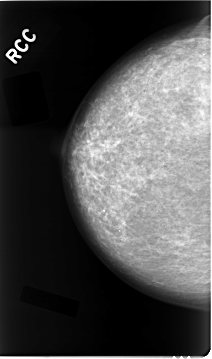

Digital Database for Screening Mammography

Volume: cancer_02 Case: C-0023-1

RIGHT_CC LINES 4664 PIXELS_PER_LINE 2744 BITS_PER_PIXEL 12 RESOLUTION 50 NON_OVERLAY

RIGHT_MLO LINES 4680 PIXELS_PER_LINE 2680 BITS_PER_PIXEL 12 RESOLUTION 50 NON_OVERLAY